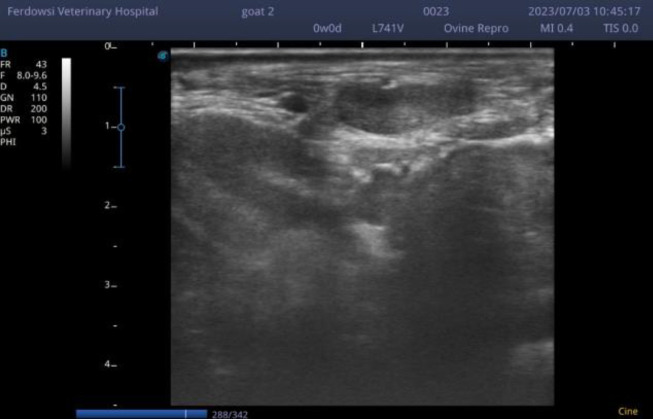

Methods: Thirty milking Saanen goats were evaluated in the study. Milk sampling from each teat was performed under standard conditions for bacteriological culture and somatic cell count (SCC). A 7.5 MHz linear transducer was used for the ultrasonography of teats with the water bath technique, and supramammary lymph nodes and udder's tissues were imaged using a 10 MHz linear transducer with direct contact. The length, height, area, and echogenicity of each lymph node and the teat canal wall diameter were measured using ImageJ 1.47v on the ultrasonography scanned images and analyzed by SPSS software.

Results: There was no significant relationship between the dimension of the supramammary lymph nodes and SCC or culture. Age had a positive relationship with lymph node size. No significant relationship was seen between the size of the supramammary lymph node before and after the treatment. Supramammary lymph nodes' echogenicity of the quarter with subclinical mastitis and healthy ones represented no significant difference before and after the treatment.

Conclusion: Ultrasonography of the udder, teat, mammary gland, and supramammary lymph nodes is a safe and non-invasive method for visualizing separate structures. The positive relationship between SCC and milk echogenicity as well as supramammary lymph nodes dimension, and age was described.